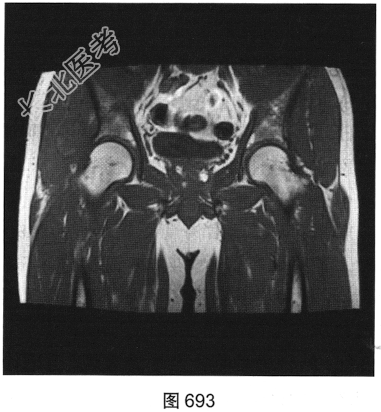

- [材料题] 患者为中年男性,发现右髋部外上方包块伴疼痛3周,以胀痛为主,包块大小为5cm×4cm,质硬,无发热、流脓流血,右下肢关节的感觉、活动、血运正常,自服止痛药治疗,疼痛稍有所缓解。查体:皮肤黏膜色泽正常,浅表淋巴结未触及,局部皮温稍高,皮肤无溃疡。

- 多项选择题2.[提示]患者行MRI平扫及增强扫描,见图692~图697。患者MRI平扫及增强扫描图像有哪些阳性表现( )

A、肿块边界不清,信号不均匀

B、肿块周围水肿明显

C、增强扫描肿块呈均匀强化

D、肿块边界清楚,信号均匀

E、增强扫描肿块及周围软组织呈明显不均匀强化

F、与邻近肌肉相比,T1WI呈等信号;T2压脂序列呈明显高信号